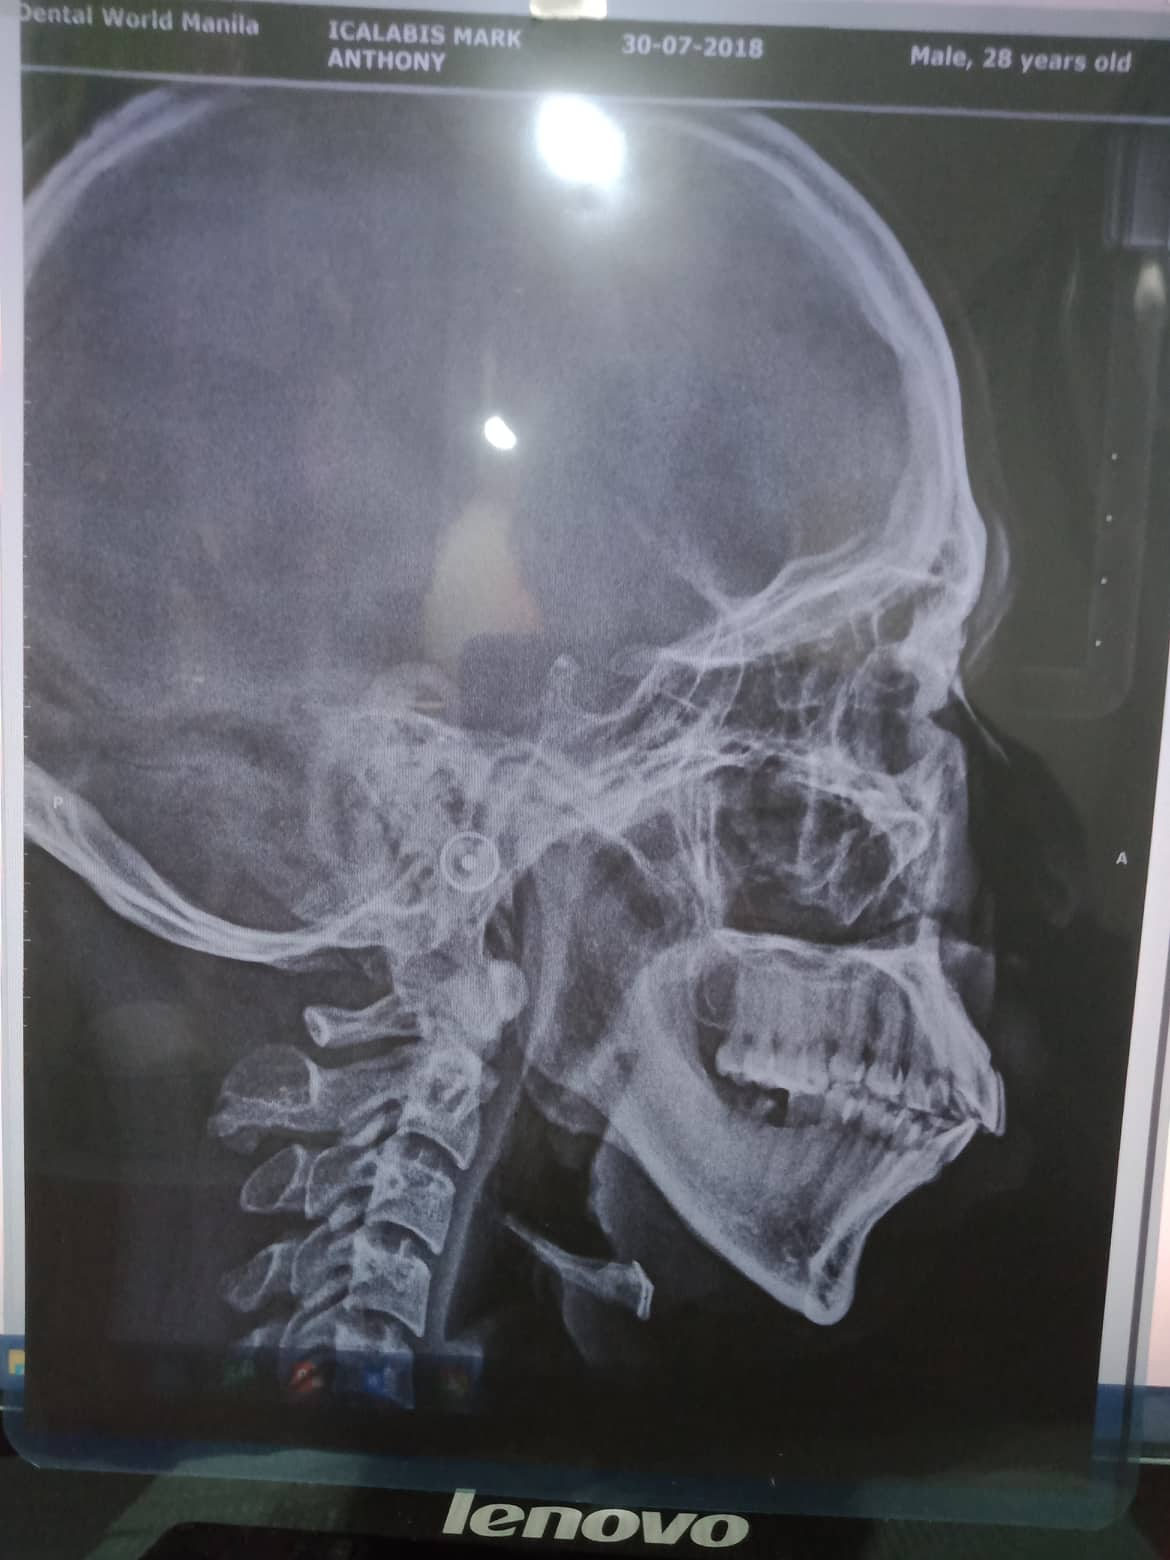

Edit Record Check our patient data records. Add patient information Patient Info Profile picture Last Name First Name Middle Name Birthdate Age Street Barangay City Country Zip Code Contact number Email Procedure 07/31/21 adj 16x22 UL 09/24/21- removal of lower braces exo 46/ upper adjustment chain 10/23/21- removal of braces upper and lower (for resto: 36/37/47 RCT #11- open canal 26mm= camphenol 11/3/21- 26mm yellow and white file apexcal composite veneer #11 11/08/21 - red file/ laser RCt tx for obturation next meeting 11/13/21 - obturation 26mm with restoration lingual pit 03/5/22- LC 26 Lingual pit, Occ/ Op File icalabisrct11.jpg File 2 301088955_824076712092412_6089268001725499639_n.jpg File 3 301583710_588567209482622_936847165020659250_n.jpg File 4 301875545_1490603051363326_3867455551585293159_n.jpg File 5 302308769_1073326889984866_975291161993186277_n.jpg File 6 File 7 File 8 File 9 File 10 File 11 File 12 File 13 File 14 File 15 File 16 File 17 File 18 File 19 File 20 Retain Record Retain Record Yes No Save Your Changes